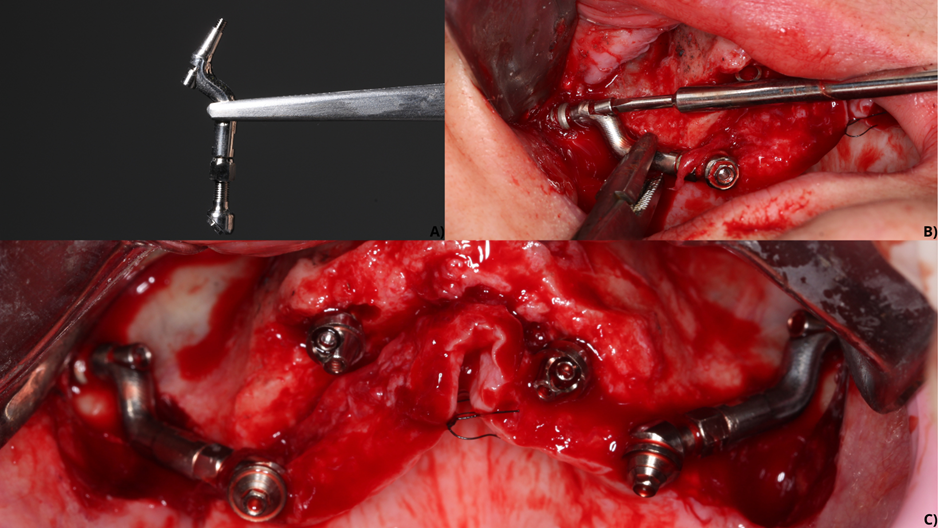

Seguindo o fluxo cirúrgico pós osteotomia, iniciou-se o processo de fresagem no processo maxilar do osso zigomático com as brocas do kit cirúrgico do pilar Z, conforme a sequência de fresas lança, fresa com espessura de 3,5 mm e por fim de 4,0 mm, todas trabalhadas até a profundidade de 15 mm em osso. Medidas estas que correspondiam ao diâmetro e altura dos implantes selecionados para essa região. Bilateralmente foram instalados implantes Due Cone de 4×15 mm, ambos com 45N de torque após instalação completa (Figura 6).

Definidas as posições de fresagem dos implantes anteriores em região de pilar canino, iniciou-se o processo utilizando kit cirúrgico convencional Implacil De Bortoli, repetindo em ambos os quadrantes superiores. Foram selecionados para esta área implantes de 4×9 mm, porém, no decorrer cirúrgico mudanças foram feitas. No segundo quadrante, no momento da fresagem com a broca lança foi possível descer com profundidade de 11 mm, sendo assim instalado implante de 4×11 mm com torque de 45N. Em primeiro quadrante, a profundidade manteve-se conforme a planejada previamente, de 9 mm. Porém, o osso nesta região se apresentava mais medular do que o previsto com os exames de imagem. Foi realizada a fresagem com a broca de 4mm e instalação do implante de 4×9 mm. Entretanto, o mesmo apresentou torque de 20N. Optou–se então pela remoção do implante já instalado e troca pelo implante de 4,5×9 mm em subfresagem. Mesmo assim, o torque de 20N permaneceu. Foi finalizada então a instalação dos quatro implantes propostos para suporte da prótese (Figura 7).

Com implantes devidamente instalados em suas áreas propostas, houve uma discussão entre os professores presentes na sala de cirurgia, alunos e cirurgiões, com a concordância de todos sobre prosseguir com o planejamento de carga imediata mesmo com implante do segundo quadrante com torque abaixo de 32N. Seguindo o fluxo planejado, foram feitos ajustes para melhorar o posicionamento do componente protético dos implantes zigomáticos, o pilar Z, para que o mesmo se estabilizasse rente a face vestibular óssea e com saída de seu componente o mais posterior possível. Para isto, foi feita nova osteotomia com a broca Maxcut revestida em zircônia, viabilizando melhor acomodação e função do componente protético. Após ajustes, o pilar Z foi instalado bilateralmente. Observando a necessidade de maior apoio e suporte protético, foi decidido por utilizar mini pilar angulado em 17° em ambos os implantes anteriores (Figura 8).